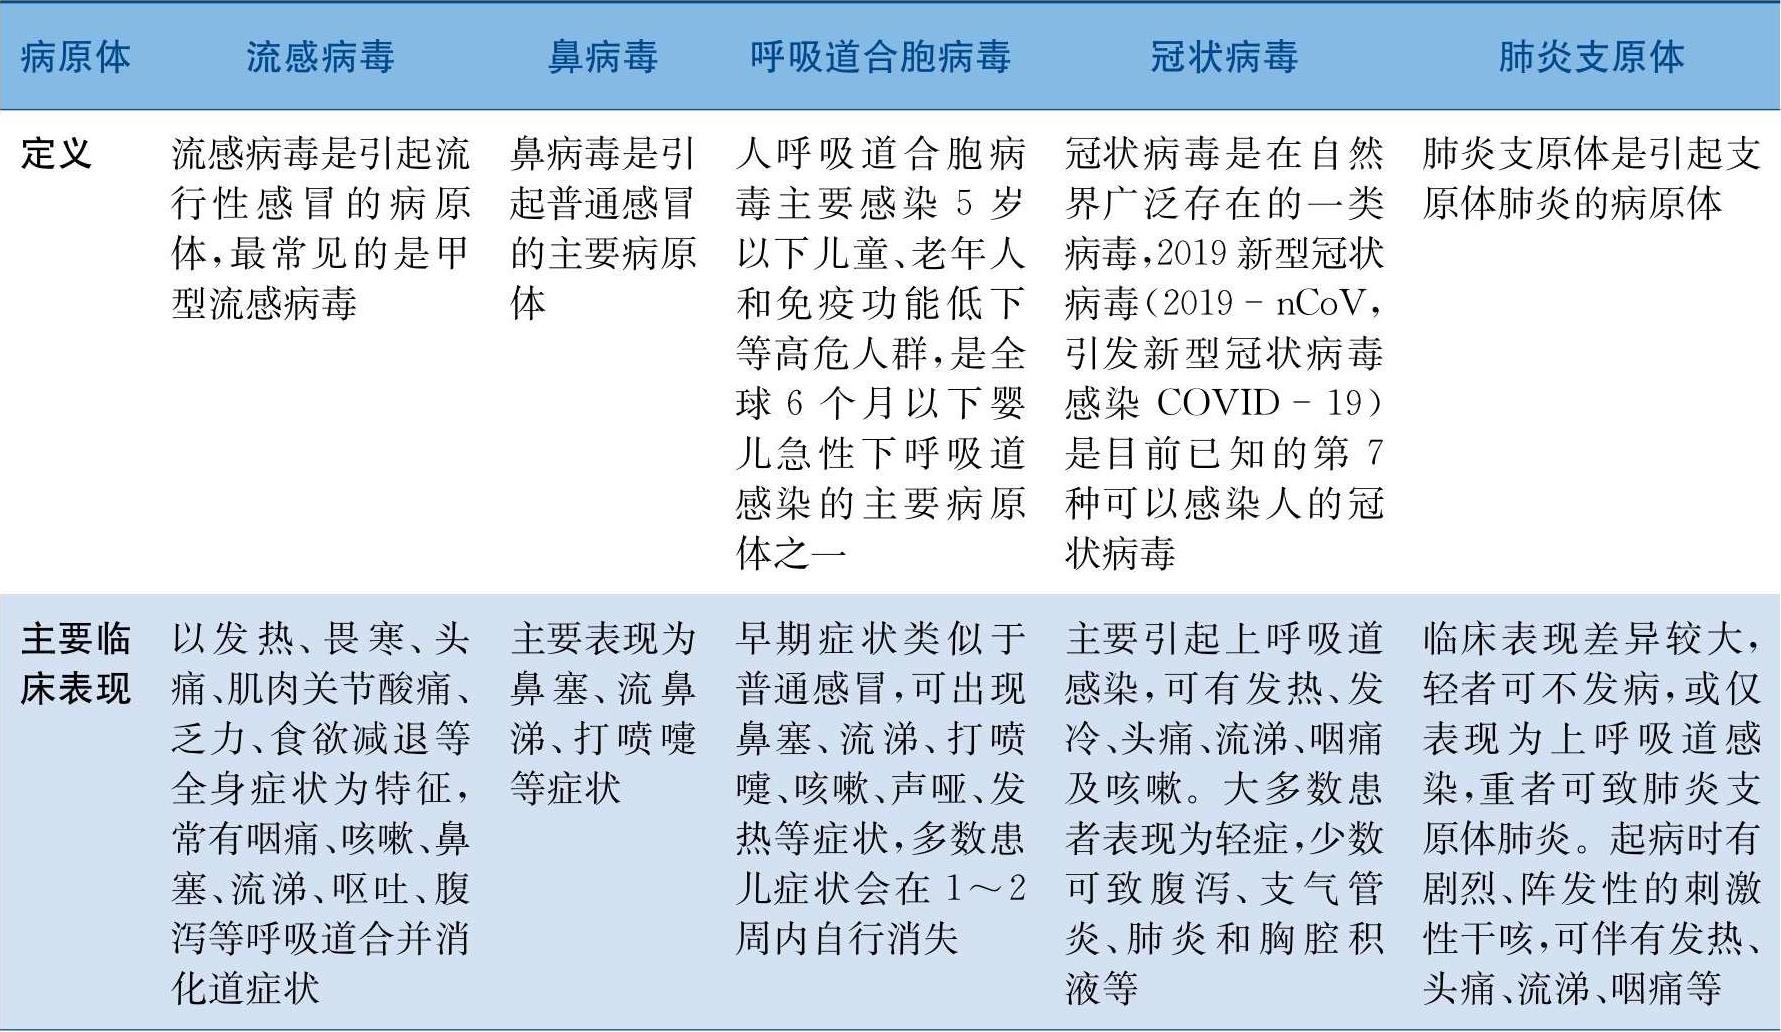

表1 不同呼吸道病原体的特点

续表